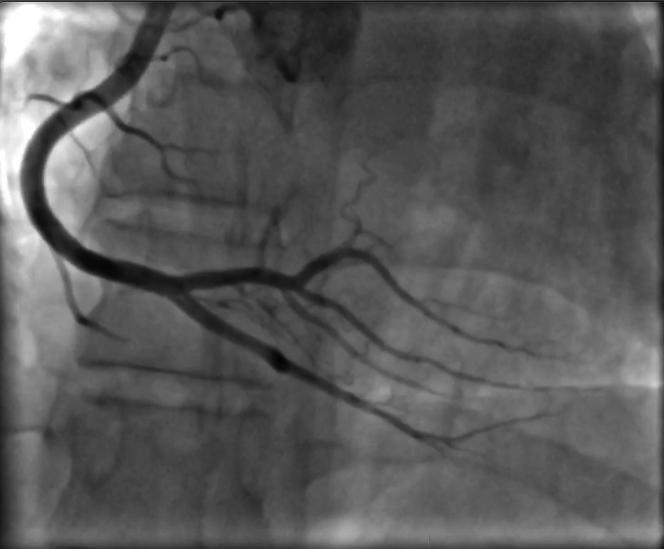

We report a case of spontaneous coronary dissection (SCAD) in a 32-year-old pregnant patient during the seventh month of her second pregnancy. A 32-year-old pregnant woman in the 28th week of gestation was referred to our intensive care unit because of angina as well as elevated troponin levels. The initial electrocardiogram and transthoracic echocardiogram (TTE) were normal. Four hours after admission, the patient experienced angina with ST-segment elevation, and the TTE showed de novo apical hypokinesia. The episode lasted approximately 10 minutes, with subsequent resolution of the ST-segment elevation. An emergency coronary angiogram revealed dissection of the left anterior descending artery. A conservative approach with aspirin monotherapy was chosen. Follow-up TTE at 3 months revealed full recovery of left ventricular function. A multidisciplinary approach is crucial in pregnancy-associated SCAD. Conservative management is generally recommended because of the potential for angiographic healing, with percutaneous coronary intervention reserved for severe cases.

我们报告一例32岁孕妇在其第二次怀孕第七个月时发生自发性冠状动脉夹层(SCAD)的病例。一名妊娠28周的32岁孕妇因心绞痛以及肌钙蛋白水平升高被转诊至我们的重症监护病房。最初的心电图和经胸超声心动图(TTE)均正常。入院4小时后,患者出现伴有ST段抬高的心绞痛,TTE显示新发心尖运动减弱。该发作持续约10分钟,随后ST段抬高消失。急诊冠状动脉造影显示左前降支动脉夹层。选择了阿司匹林单药治疗的保守方法。3个月后的随访TTE显示左心室功能完全恢复。多学科方法对于妊娠相关的SCAD至关重要。由于血管造影有愈合的可能,一般建议采取保守治疗,对于严重病例则保留经皮冠状动脉介入治疗。